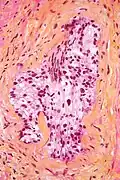

HPS stain

In histology, the HPS stain, or hematoxylin phloxine saffron stain, is a way of marking tissues.

HPS is similar to H&E, the standard bearer in histology. However, it differentiates between the most common connective tissue (collagen) and muscle and cytoplasm by staining the former yellow and the latter two pink,[1] unlike an H&E stain, which stains all three pink.